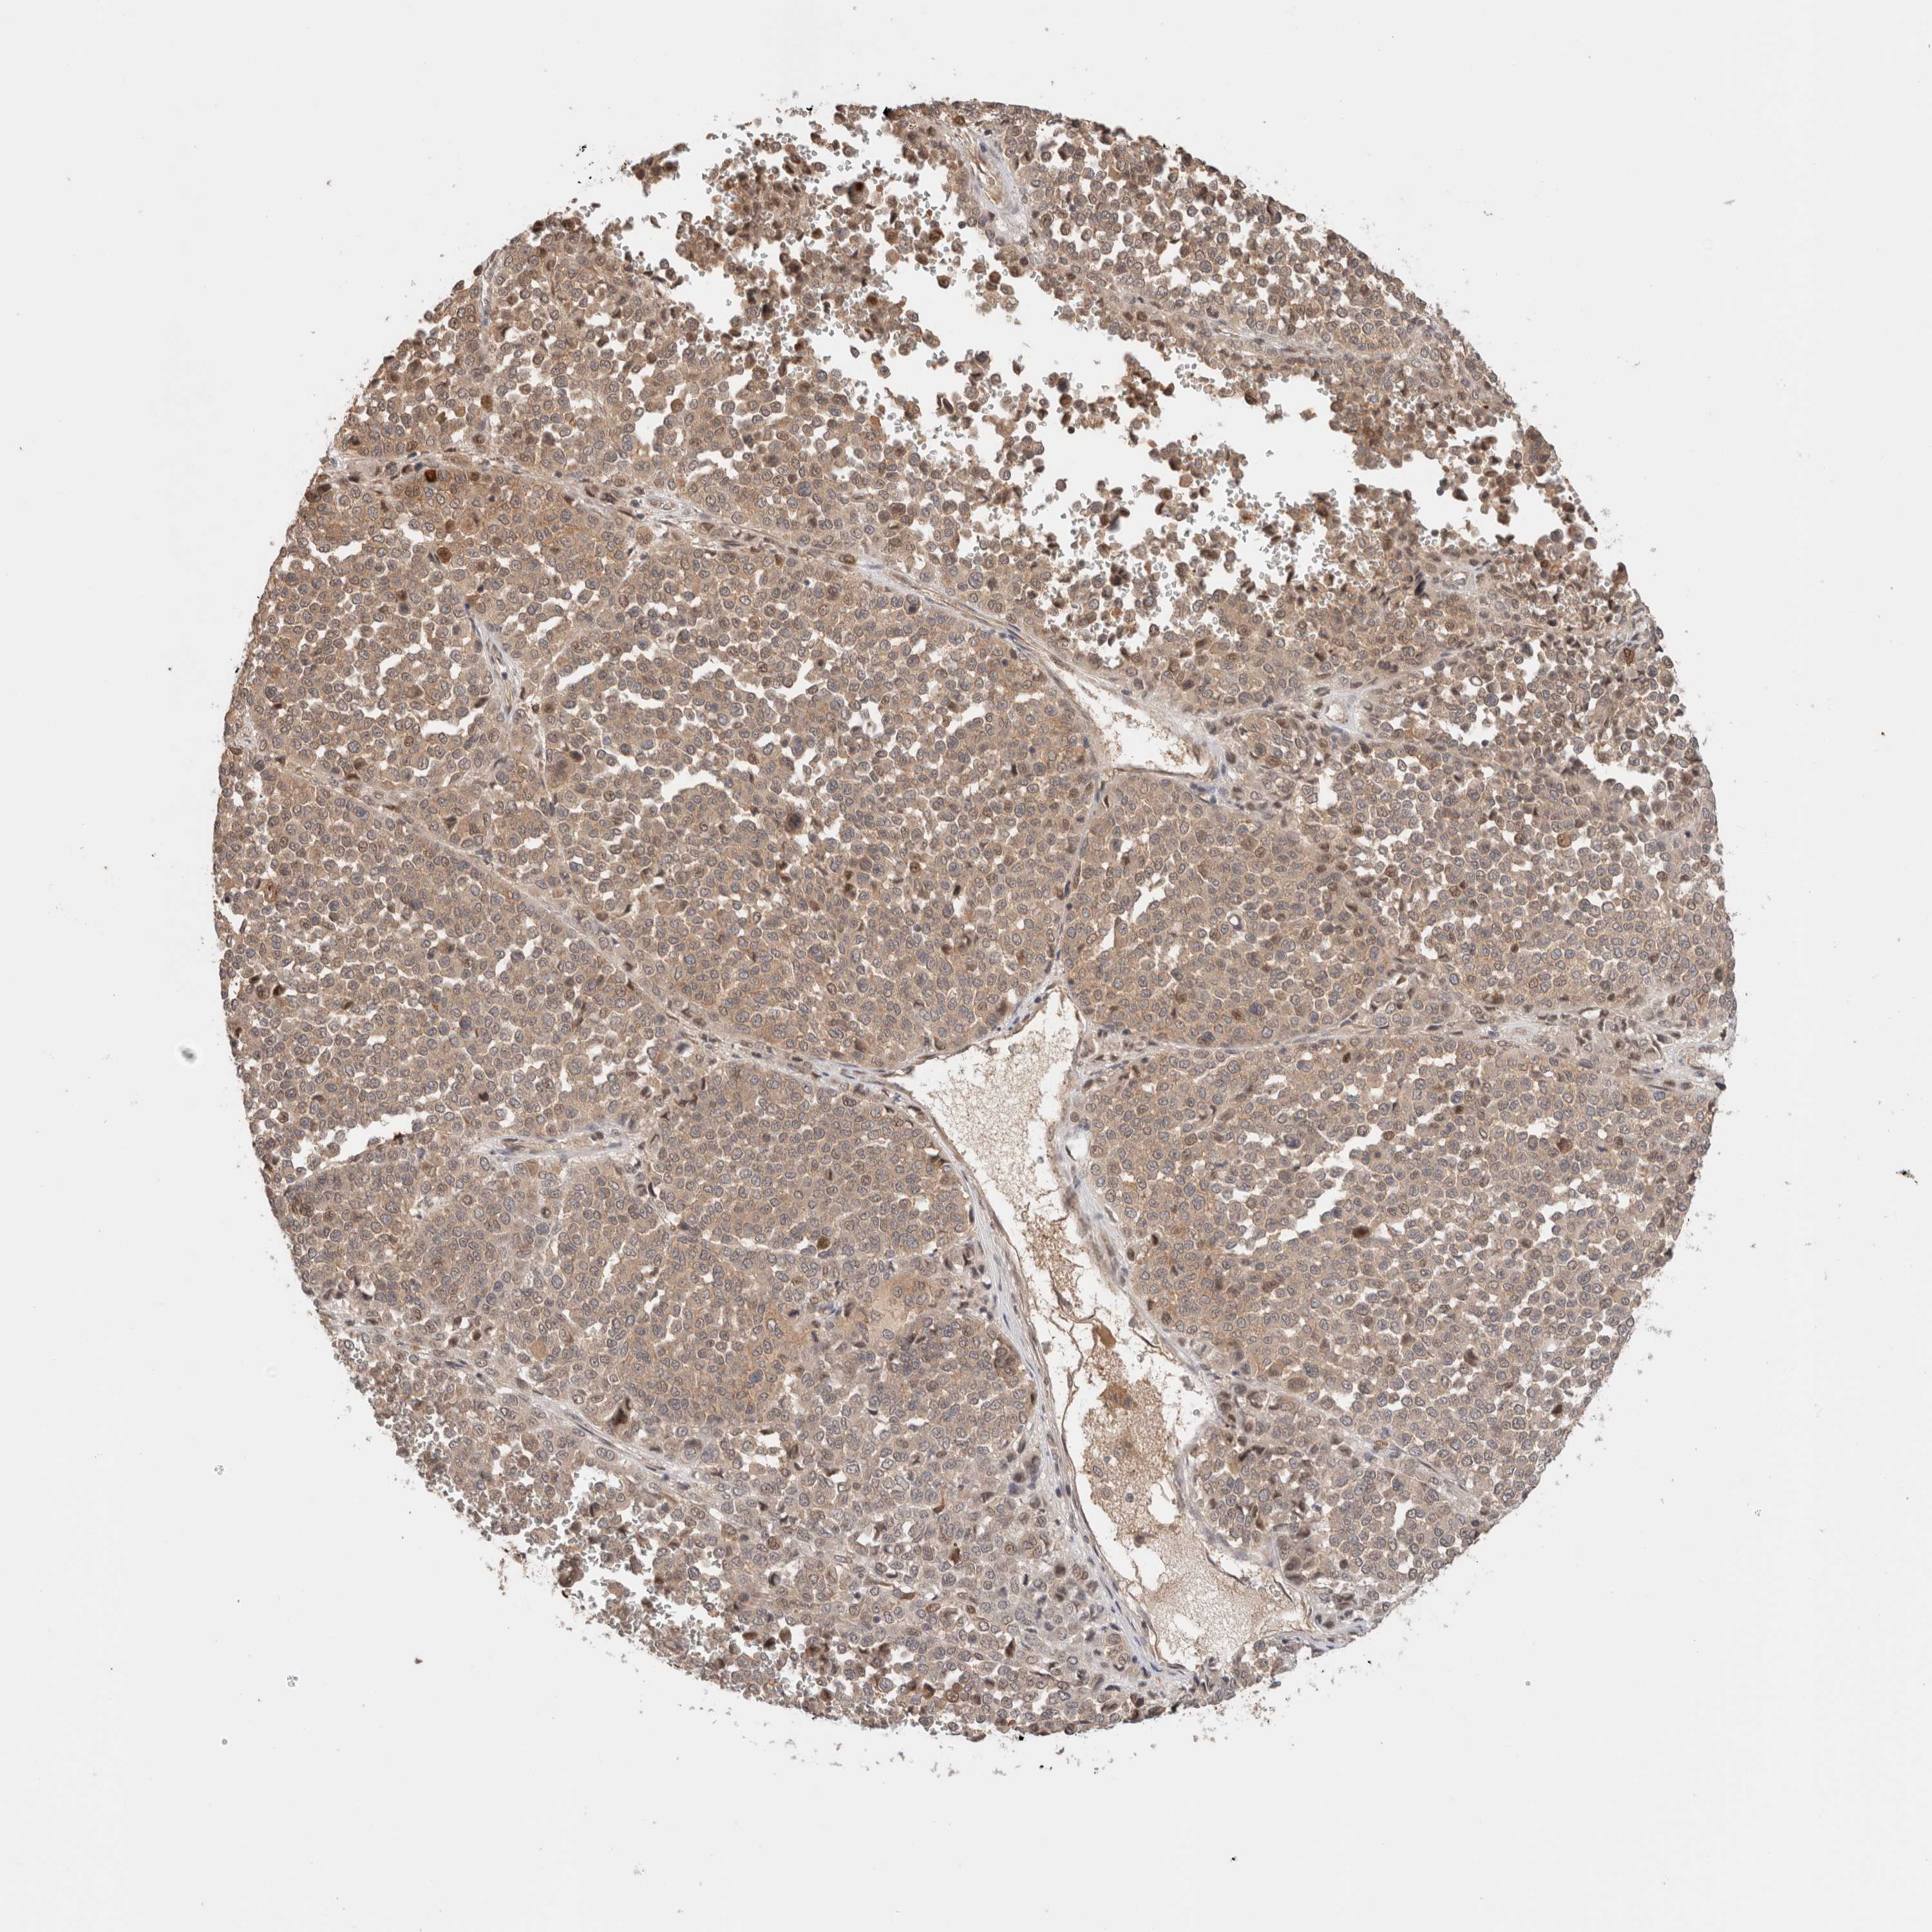

MELANOMA - Protein expressioni

A mouse-over function shows sample information and annotation data. Click on an image to view it in a full screen mode. Samples can be filtered based on level of antibody staining by selecting one or several of the following categories: high, medium, low and not detected. The assay and annotation is described here.

Note that samples used for immunohistochemistry by the Human Protein Atlas do not correspond to samples in the TCGA dataset.

Antibody stainingi

Antibody staining in the annotated cell types in the current human tissue is reported as not detected, low, medium, or high, based on conventional immunohistochemistry profiling in selected tissues. This score is based on the combination of the staining intensity and fraction of stained cells.

Each image is clickable and will lead to virtual microscopy that enables deeper exploration of all samples and also displays staining intensity scores, fraction scores and subcellular localization as well as patient and tissue information for each sample.

Antibody HPA024046

Antibody HPA024503

Antibody HPA024772

Staining

High

Medium

Low

Not detected

Intensity

Strong

Moderate

Weak

Negative

Quantity

>75%

75%-25%

<25%

None

Location

Nuclear

Cytoplasmic/membranous

Cytoplasmic/membranous,nuclear

Malignant melanoma, NOS

Malignant melanoma, Metastatic site